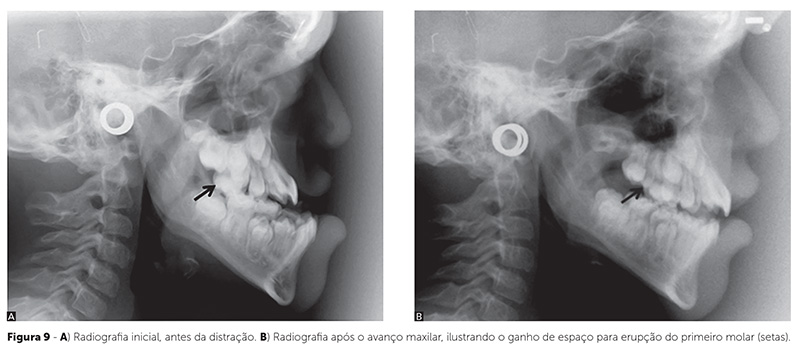

Tanto os pacientes com fendas quanto os que apresentam síndromes, experimentam estabilidade resultante dos tratamentos com, respectivamente, avanço da maxila e da face média (Fig. 8). A grande quantidade de formação óssea na área pterigomaxilar é o acontecimento crucial que favorece esse prognóstico. Além do volume, o tipo de osso lamelar denso — verificado em exame histológico e radiográfico11,16 — fortalece o prognóstico. Essa formação óssea local também possibilita espaço adicional para a erupção dentária (Fig. 9)28.